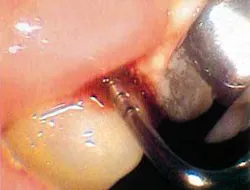

But before we discuss soft tissue invasion, I'd like to talk a little about refractory periodontitis. We've all had cases where the patient fails to respond to treatment. We do everything we can think of to stop the attachment loss, yet at each recall, the probe slides a little farther into the pockets and the radiographs look bleaker (see Figures 1 and 2).